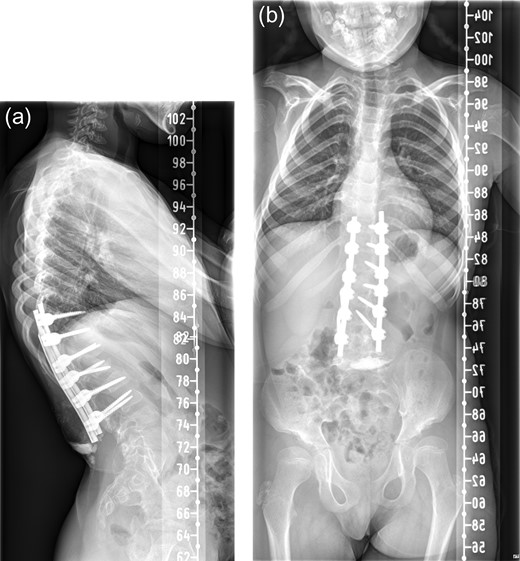

Patient was reviewed 1 month after the surgery and radiographs (Fig. 3a and b) revealed heterotopic ossification in the paraspinal soft tissue. Matured mineralized bone was clearly seen near the distal end of the spinal construct. Wound was healed and there was no further discharge. No further intervention has been planned as patient remains asymptomatic with good radiographic correction of kyphosis.

One month postoperative spine radiograph in (a) lateral view and (b) anteroposterior view showing heterotopic ossification.